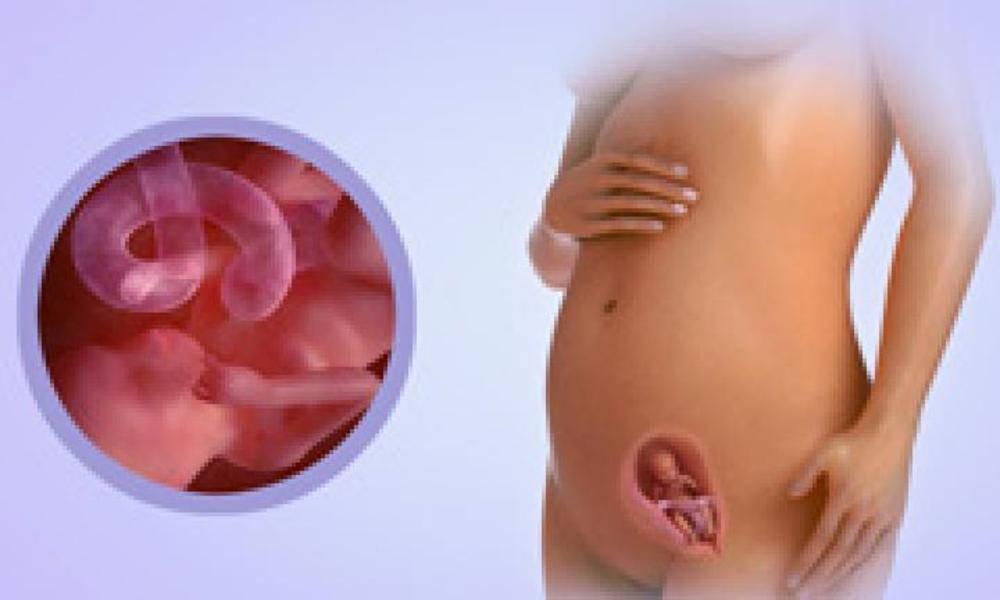

Расположение плода на 15-й неделе беременности: фотографии и иллюстрации

Раздел: Идеи и советы